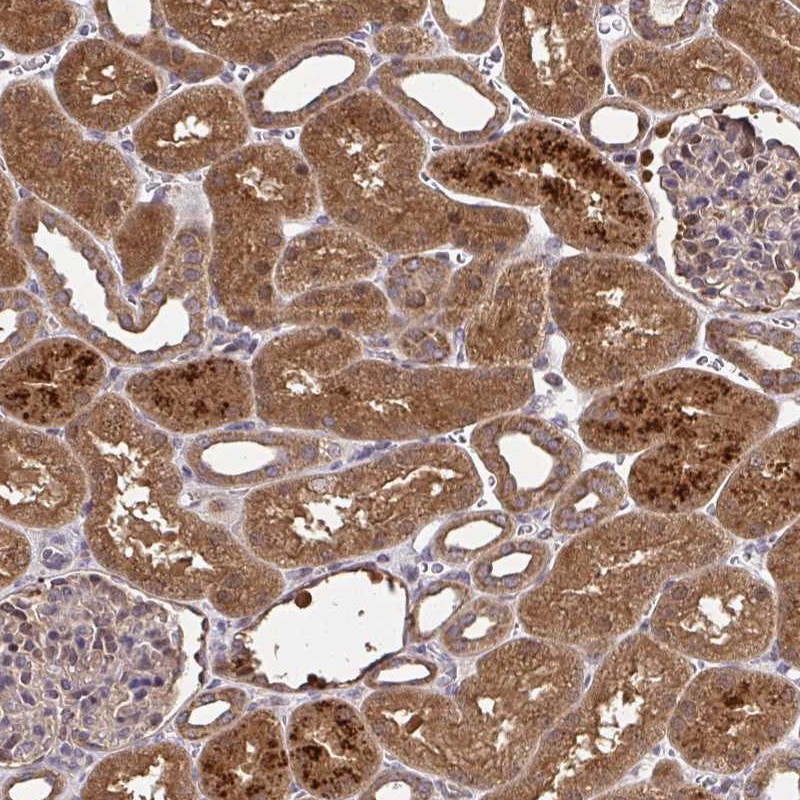

Immunohistochemical staining of human kidney shows strong cytoplasmic positivity in cells in tubules.